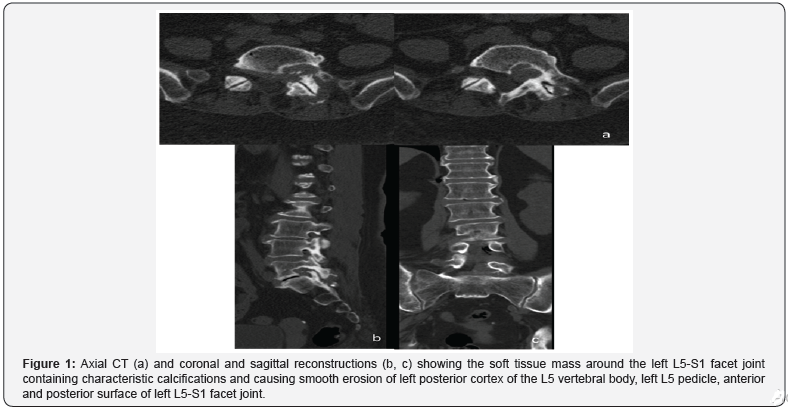

CT and MRI images (Figures 1 & 2) demonstrate a heterogeneous mass centered on left L5-S1 facet joint with epidural extension and posterior paraspinal component. CT images show a few faint punctuate calcifications within a predominantly non-calcified mass causing chronic smooth erosion of left posterior cortex of the L5 vertebral body, left L5 pedicle, anterior and posterior surface of left L5-S1 facet joint. On MRI the mass consists of a tissue with predominantly dark signal on T1, T2 and T2 FS sequences with little foci of contrast enhancement. The epidural component of the mass spreads along the left anterior wall of the spinal canal, compresses the left S1 nerve root within the neural foramen. The posterior paraspinal component pushes back the left multifidus and longissimus thoracis muscle. The patient underwent the surgical removal of the tumor with osteoplasty of bone defect at the N.N. Blokhin National Medical Cancer Center.